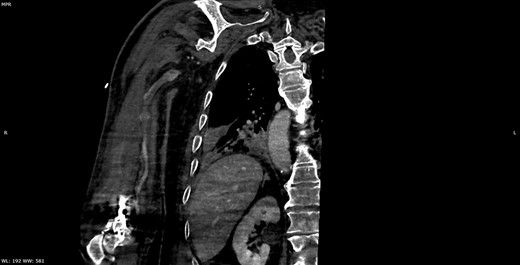

Multiplanar reformation image shows severe near occlusion 6-mm stenosis of the ulnar artery.

Multiplanar reformation image shows filling defect in the right axillary vein consistent with thrombosis.